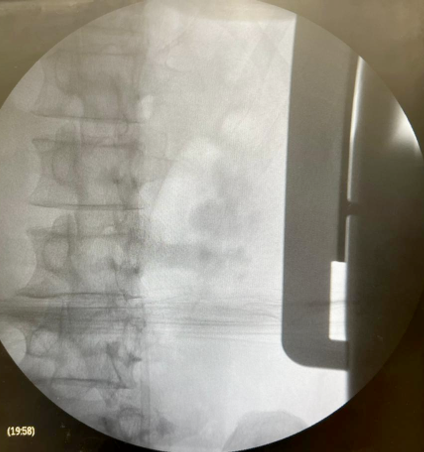

Imagem Inicial e final: